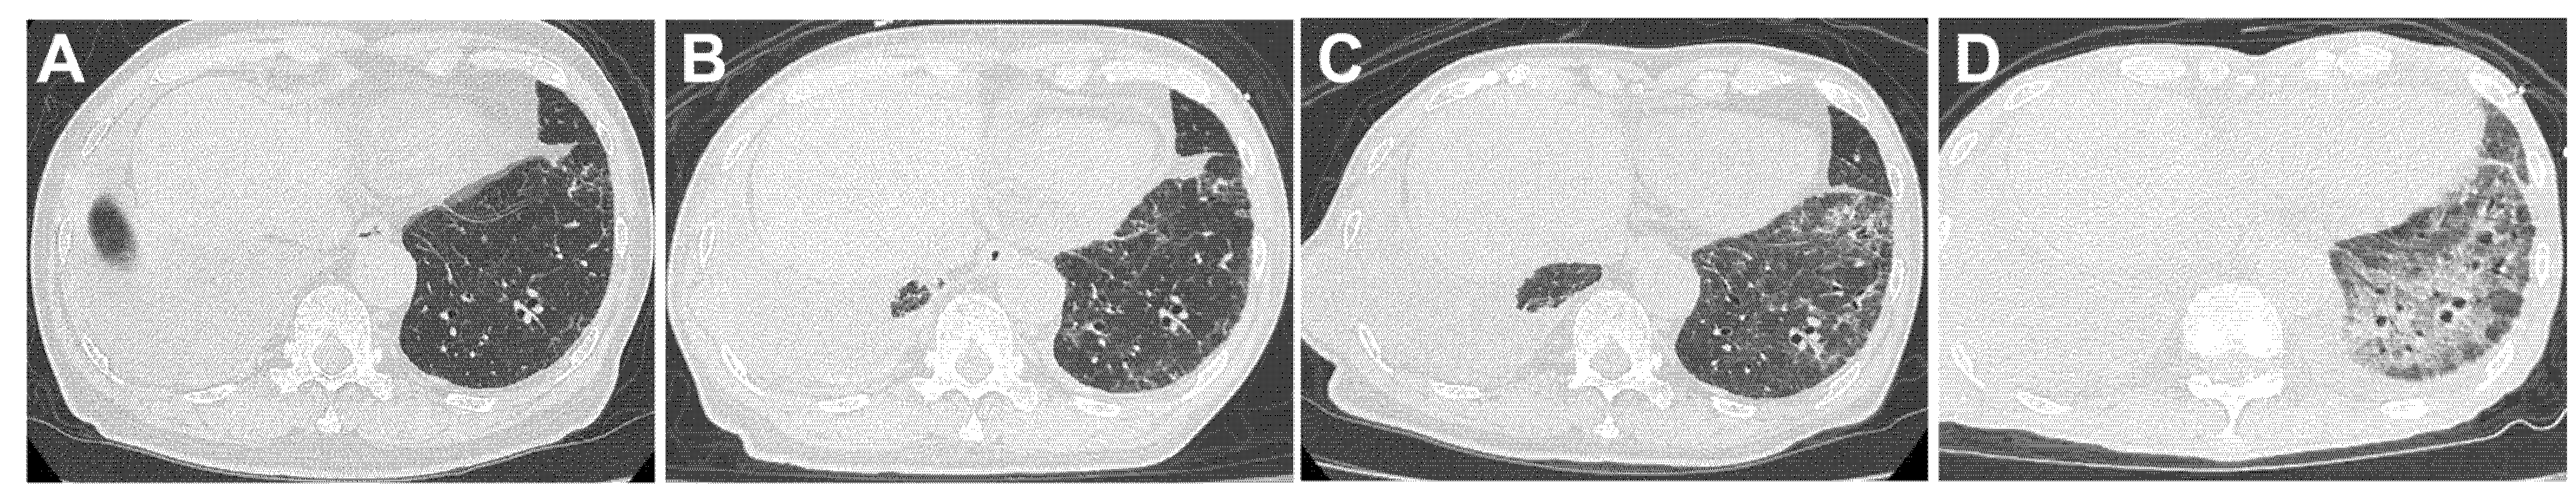

4.4.3. Patient 3 (Figure 4, Table 4)